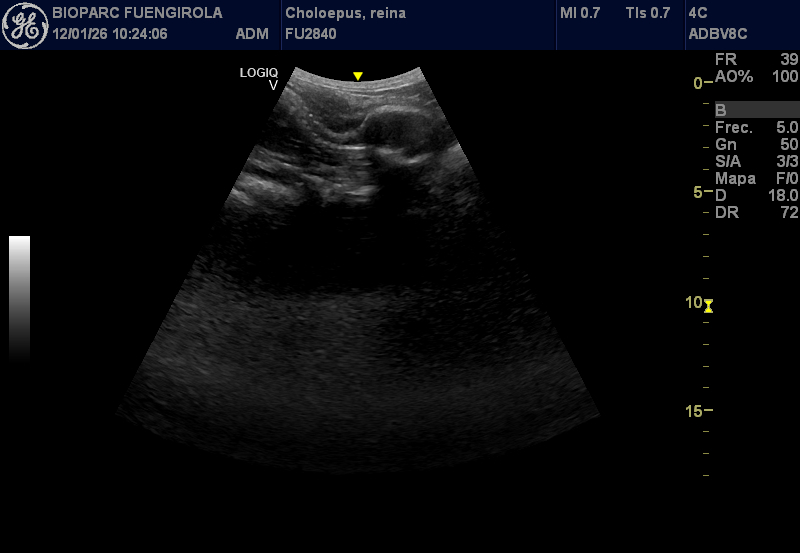

El seguimiento de la gestación se está realizando dentro de los protocolos habituales de cuidado y bienestar del animal, integrando revisiones veterinarias voluntarias y sin ningún tipo de riesgo. Entre ellas se incluyen ecografías realizadas como parte de su rutina diaria, posibles gracias a un avanzado programa de entrenamiento veterinario desarrollado por los equipos de Zoología y Veterinaria de BIOPARC Fuengirola.

Gracias a un proceso progresivo de desensibilización y familiarización, los cuidadores han logrado que Reina acepte de forma natural la presencia del equipo veterinario y el contacto necesario para la exploración abdominal. Para ello, se han simulado previamente las condiciones reales del procedimiento mediante el uso de instrumentos similares a la sonda ecográfica, presiones controladas y la aplicación de geles, siempre sin contacto protegido y bajo estrictas medidas de seguridad. Este trabajo permite monitorizar de forma regular el desarrollo fetal, la frecuencia cardiaca y el estado general de la madre sin alterar su comportamiento.

El embarazo comenzó a sospecharse tras el registro detallado de las cópulas y la posterior observación de una leve distensión abdominal en los últimos meses, apenas perceptible para ojos no expertos. Esta discreción no es casual: se trata de una adaptación evolutiva que permite a los perezosos pasar desapercibidos frente a depredadores como grandes rapaces, felinos o serpientes constrictoras. Los controles veterinarios confirman que el feto se desarrolla con normalidad y a buen ritmo, mientras que Reina mantiene una conducta, alimentación y rutina completamente estables.

El periodo de gestación de esta especie es especialmente largo, con una media estimada de entre 330 y 350 días, aunque existen importantes variaciones descritas en la literatura científica. En estos momentos, los especialistas sitúan a Reina en el último tercio del embarazo, una fase clave que se afronta con un seguimiento continuo y adaptado a sus necesidades.